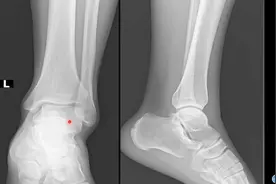

踝关节必备知识,七块跗骨的骨性标志与定位

踝关节,由胫骨、腓骨下端的关节面与距骨滑车构成,故又名距骨小腿关节。 踝关节容易发生扭伤,其中以内翻损伤最多...

踝关节(anklejoint),由胫、腓骨下端的关节面与距骨滑车... 由软骨桥相连接。病因:距骨三角骨急性骨折或慢性应力性...